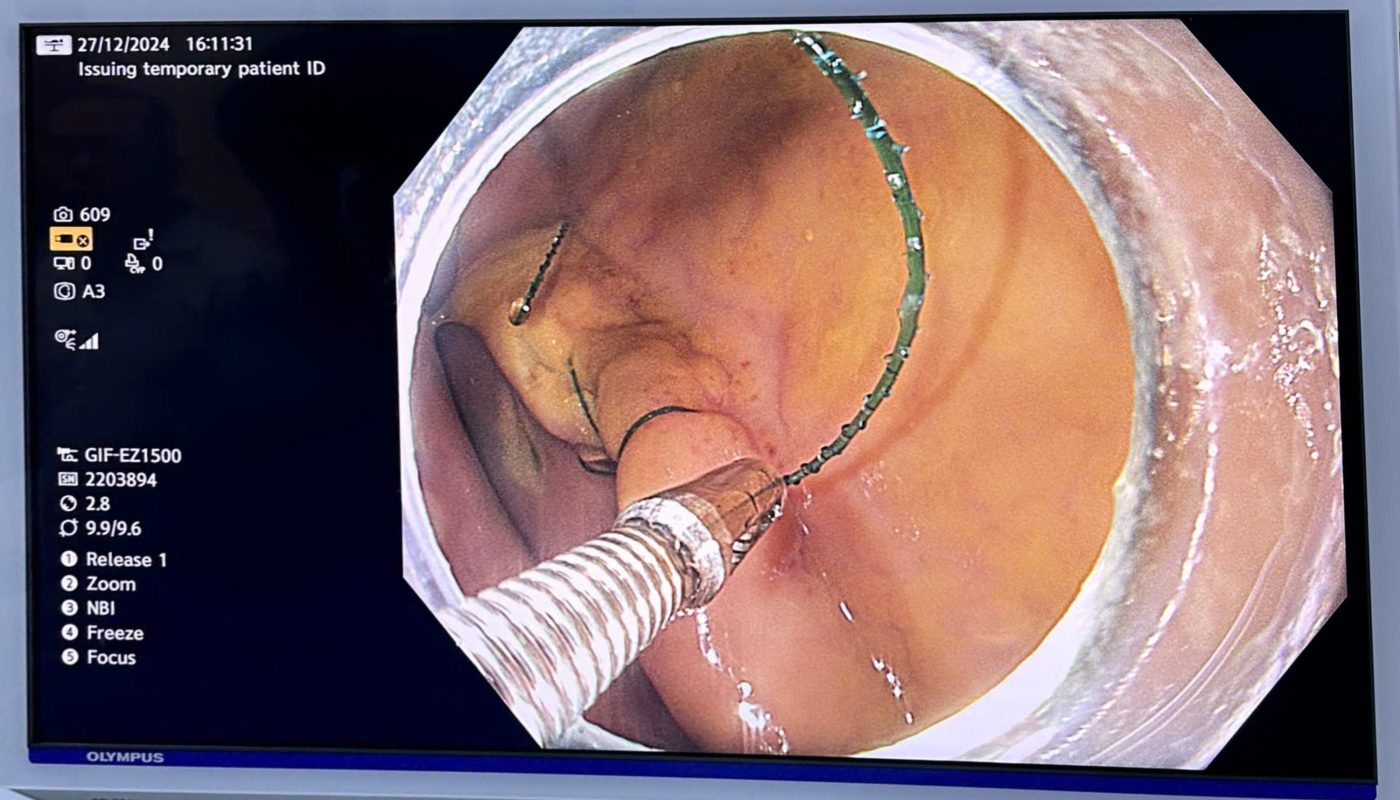

Sáng ngày 4/1/2025, tại hội trường lớn của Bệnh viện Bạch Mai (Hà Nội), Đại hội thành lập Hội Nội soi Tiêu hóa Can thiệp Việt Nam (VIGES) đã diễn ra thành công tốt đẹp, mở ra một chương mới cho ngành y học tiêu hóa tại Việt Nam.